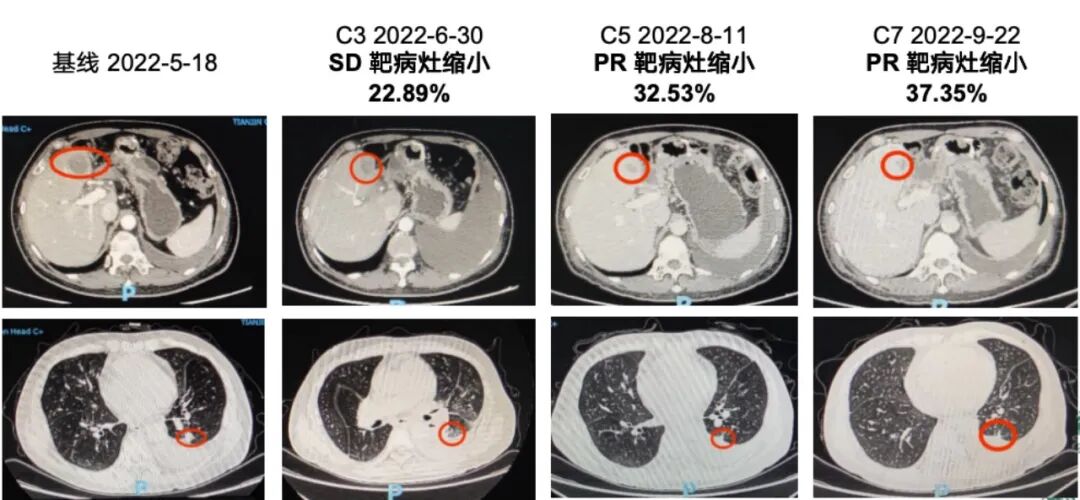

JAB-21822使用起来相对方便,患者只需在门诊开药,并且口服,不需要注射。入组时,患者的下肢肿胀症状比较明显,服药后症状都在逐渐好转。在服药大约一个月后,就看到患者的体力明显改善(1-0),肿瘤标志物下降(CA19-9:>20000下降到3382.6),第一次影像学评估显示,肿瘤整体缩小22.89%,第二次缩小到32.53%。最终患者的评估疗效确认达到PR状态,病情得到了有效缓解,并且在疾病缓解状态持续病程超过一年,获得了非常好的生活质量。

靶向治疗前后病灶对比

以往,如果胰腺癌患者到三线或四线治疗时,病情会迅速进展,症状较多,甚至危及生命,总体病程相对较短。这例患者在四线治疗时来我院开始使用KRAS G12C位点的靶向药物,并在之后有了很好的生活质量,即使后续出现进展,但是按照RESIST标准评估来看,并不是大面积进展。